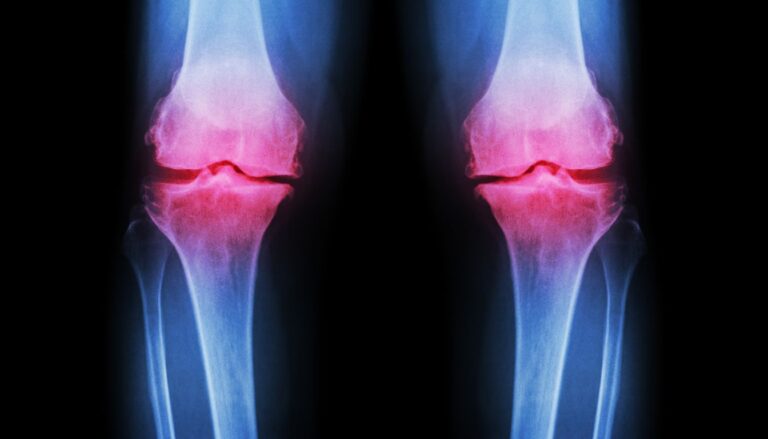

Co tak naprawdę dzieje się w naszym ciele, gdy mówimy o zroście kości po operacji haluksa? Choć proces ten może wydawać się skomplikowany, jego zrozumienie jest.

Rehabilitacja po operacji haluksa jest kluczowym aspektem, który wpływa na proces odzyskiwania pełni…